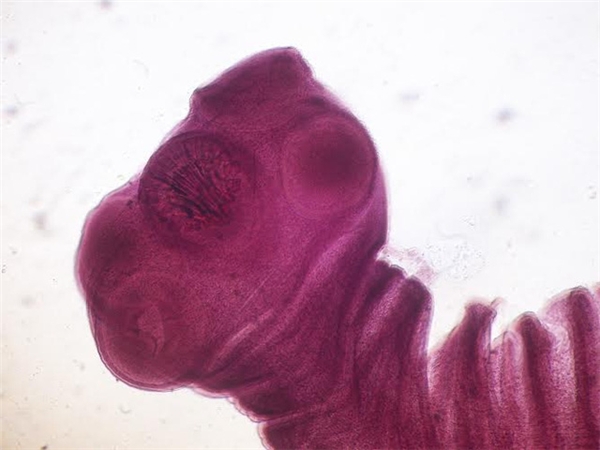

Old  Default Kinh hãi với những quái vật âm thầm ký sinh trong cơ thể người

Bài viết này sẽ không đề cập đến những sinh vật vô hại tồn tại trong cơ thể chúng ta. Những quái vật dưới đây là những ký sinh trùng đặc biệt gây hại tới cơ thể người, thậm chí có thể dẫn đến tử vong. Tốt nhất nên đề phòng đừng để những ký sinh trùng này thâm nhập vào cơ thể.

Ký sinh trùng là sinh vật siêu nhỏ thường sống ký sinh trên cơ thể vật chủ. Chúng sống và phát triển nhờ việc hút chất dinh dưỡng hay máu của vật chủ.

Chúng cư ngụ trên mọi bộ phận của con người như não, gan, phổi, mắt, ruột....và gây ra những tổn thương nghiêm trọng, có thể dẫn tới tử vong.

1. Lợn sán dây

Lợn sán dây có thể gây ra chứng động kinh và các vấn đề thần kinh khác ở người do ăn trứng có chứa ấu trùng.

Sán trưởng thành ký sinh ở ruột non. Ấu trùng sán ký sinh ở các cơ và nội tạng như não, tim, mắt.

4. Sán dây Spirometra

Sán dây Spirometra là loại kí sinh trùng có thể gây ra tình trạng viêm của các mô trong cơ thể và trong não, có thể dẫn tới tình trạng co giật, mất trí nhớ và đau đầu.

Theo các chuyên gia, loài sán này khá hiếm, vòng đời cũng như đặc điểm sinh học của nó vẫn chưa được biết đến nhiều.

Con người có thể bị nhiễm loại sán dây này do vô tình ăn phải động vật giáp xác nhỏ có nhiễm ấu trùng sán dây từ hồ nước ô nhiễm, ăn thịt sống các loài bò sát và lưỡng cư hoặc sử dụng phương thuốc chữa đau mắt bằng thịt ếch sống của Trung Quốc.

Kể từ năm 1953 tới nay, y học mới chỉ ghi nhận 300 ca nhiễm ký sinh trùng này ở người, trong đó chỉ có 2 trường hợp ở châu Âu.